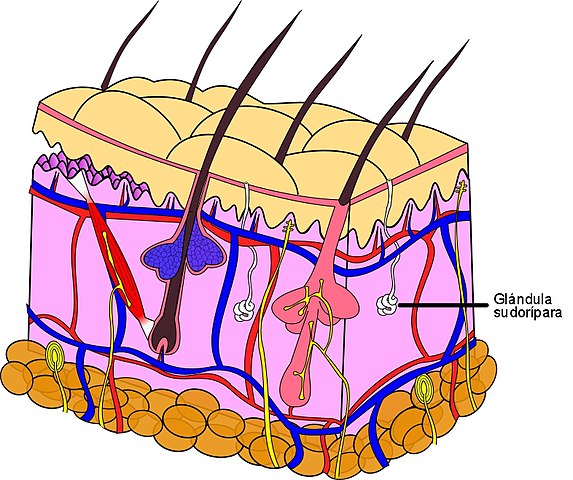

Este grupo de glándulas se caracteriza por secretar sus productos a través de conductos hacia la superficie (externa o interna) del epitelio donde se originan. La piel y el tracto digestivo, por ejemplo, reciben el sudor, la bilis y las enzimas digestivas de las glándulas sudoríparas, el hígado y el páncreas, correspondientemente.

Las glándulas sudoríparas, otro ejemplo de glándulas exocrinas, participan del control de la temperatura corporal al eliminar del cuerpo líquido que se evapora, liberando calorías.